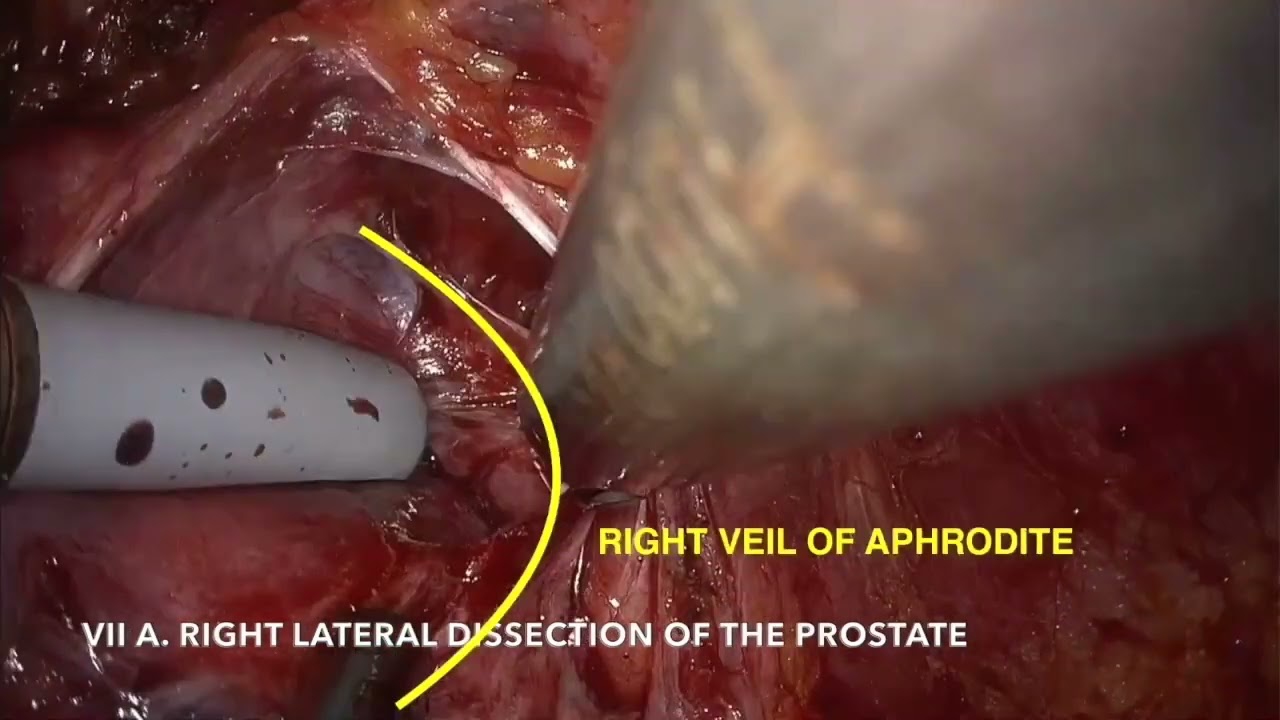

#317 Endopelvic fascia preservation nerve sparing RARP Dr. Kazuhiro Matsumoto

KS Awards, Robotics, Surgeon ';